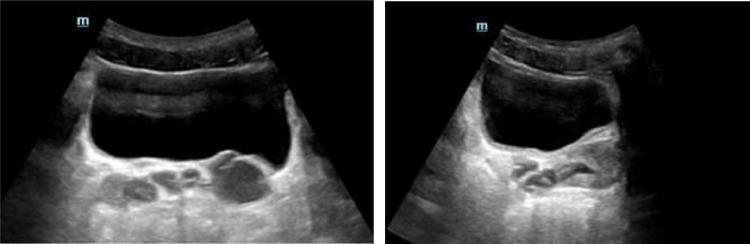

A triad of unilateral renal agenesis, ipsilateral seminal vesicle cyst and ipsilateral ejaculatory duct obstruction has been called Zinner syndrome since its first description in 1914 by Zinner. It is a very rare congenital abnormality of the male genitourinary tract due to abnormal embryologic development of the Wolffian ducts. There have been several case reports from different parts of the world about the clinical and imaging findings of these anomaly. In this case report, we present the first case report of Zinner syndrome in a 28-year-old male Ethiopian patient.

自1914年齐纳首次描述以来,单侧肾缺如、同侧精囊囊肿和同侧射精管梗阻三联征被称为齐纳综合征。它是一种非常罕见的男性生殖泌尿系统先天性异常,由中肾管胚胎发育异常引起。世界各地已有多篇关于这些异常的临床和影像学表现的病例报告。在本病例报告中,我们呈现了一名28岁埃塞俄比亚男性患者的齐纳综合征首例病例报告。